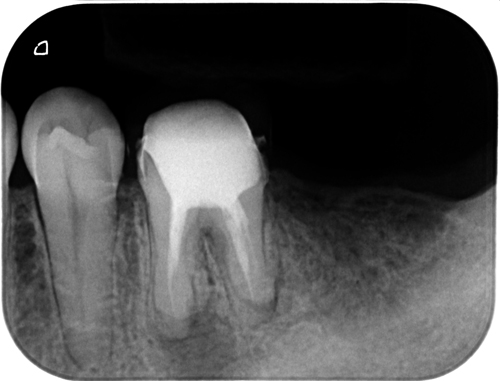

レントゲン上では、確かに大きな透過像が確認できます。一般的には、この大きさだけで「もうダメですね」と判断されることも少なくありません。

今回の歯も、既に根管治療は行われていました。しかし感染源が取り切れていない状態でした。こういうケースでは、どれだけ時間が経っても、どれだけ薬を入れても治ることはありません。再治療では、根管内の再評価と見落とされていた部分の処理を丁寧に行いました。特別なことをしたわけではありません。原因を取り除いただけです。

術後3ヶ月で透過像の改善が確認できました。